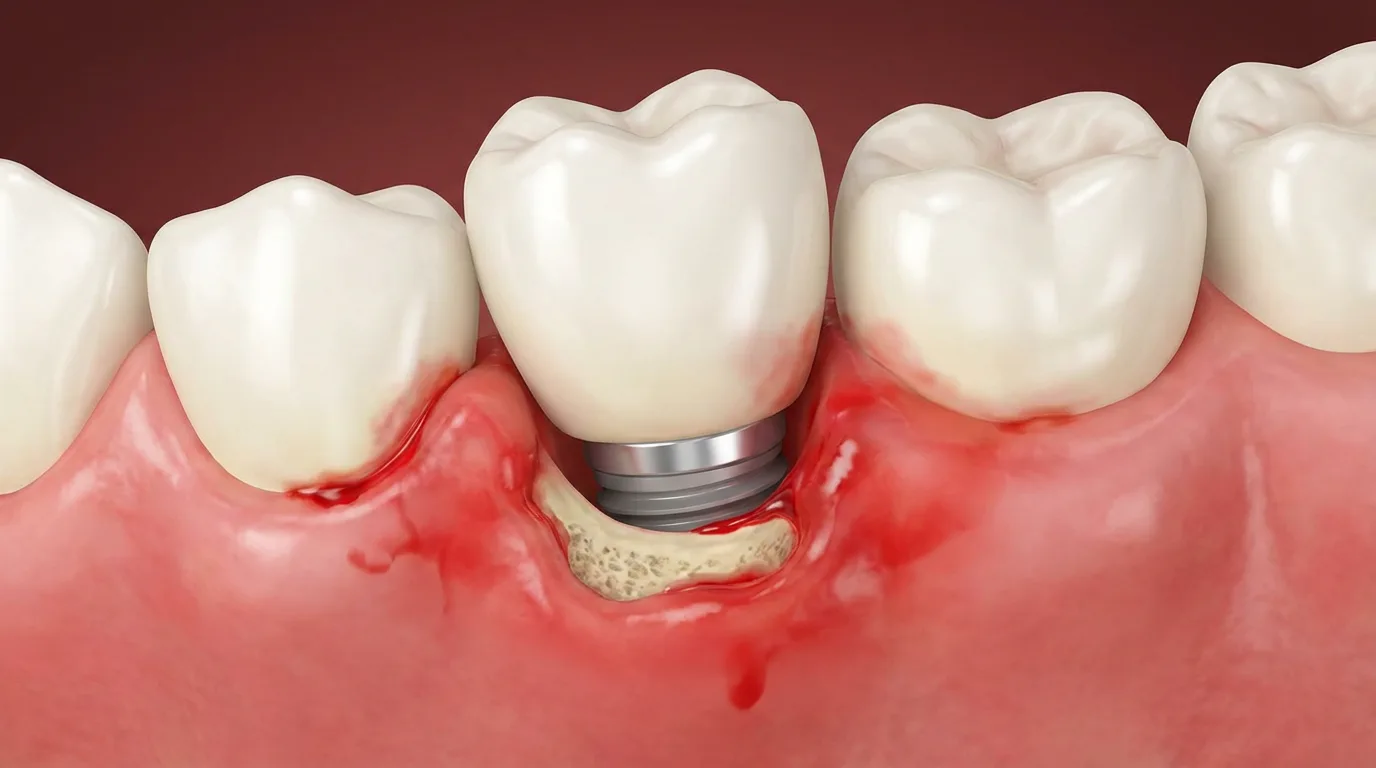

-임플란트 주변 조직에 염증이 생겨 뼈가 녹거나 흔들림이 나타나는 경우

임플란트가 실패한 부위는 뼈가 약해져 있거나 염증 흔적이 남아있는 경우가 많습니다. 따라서 재수술은 단순히 다시 심는 것이 아니라 원인을 정확히 찾고, 구조를 회복시키며, 다시 안정적인 상태로 만드는 과정이어야 합니다.